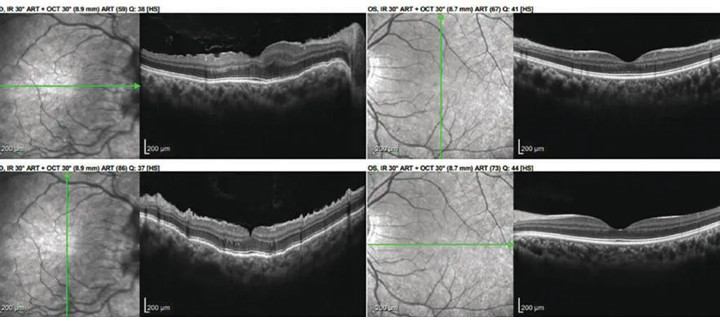

SPECTRALIS OCT macula 1 week after final argon laser photocoagulation session demonstrating improved chorioretinal contour OD.

Image courtesy: Jillian Lu, MD, Claire K. Wright, MD